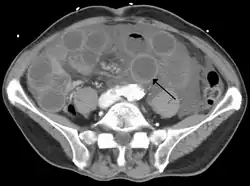

Computed tomography (CT) showing dilated loops of small bowel with thickened walls (black arrow), findings characteristic of ischemic bowel due to thrombosis of the superior mesenteric vein.

Computed tomography

Computed tomography (CT scan) is often used.[29][30] The accuracy of the CT scan depends on whether a small bowel obstruction (SBO) is present.[31]

Early findings on CT scan include:

• Intestinal mesenteric edema[29]

• Bowel dilatation[29]

• Bowel wall thickening[29]

• Intestinal mesenteric stranding[32]